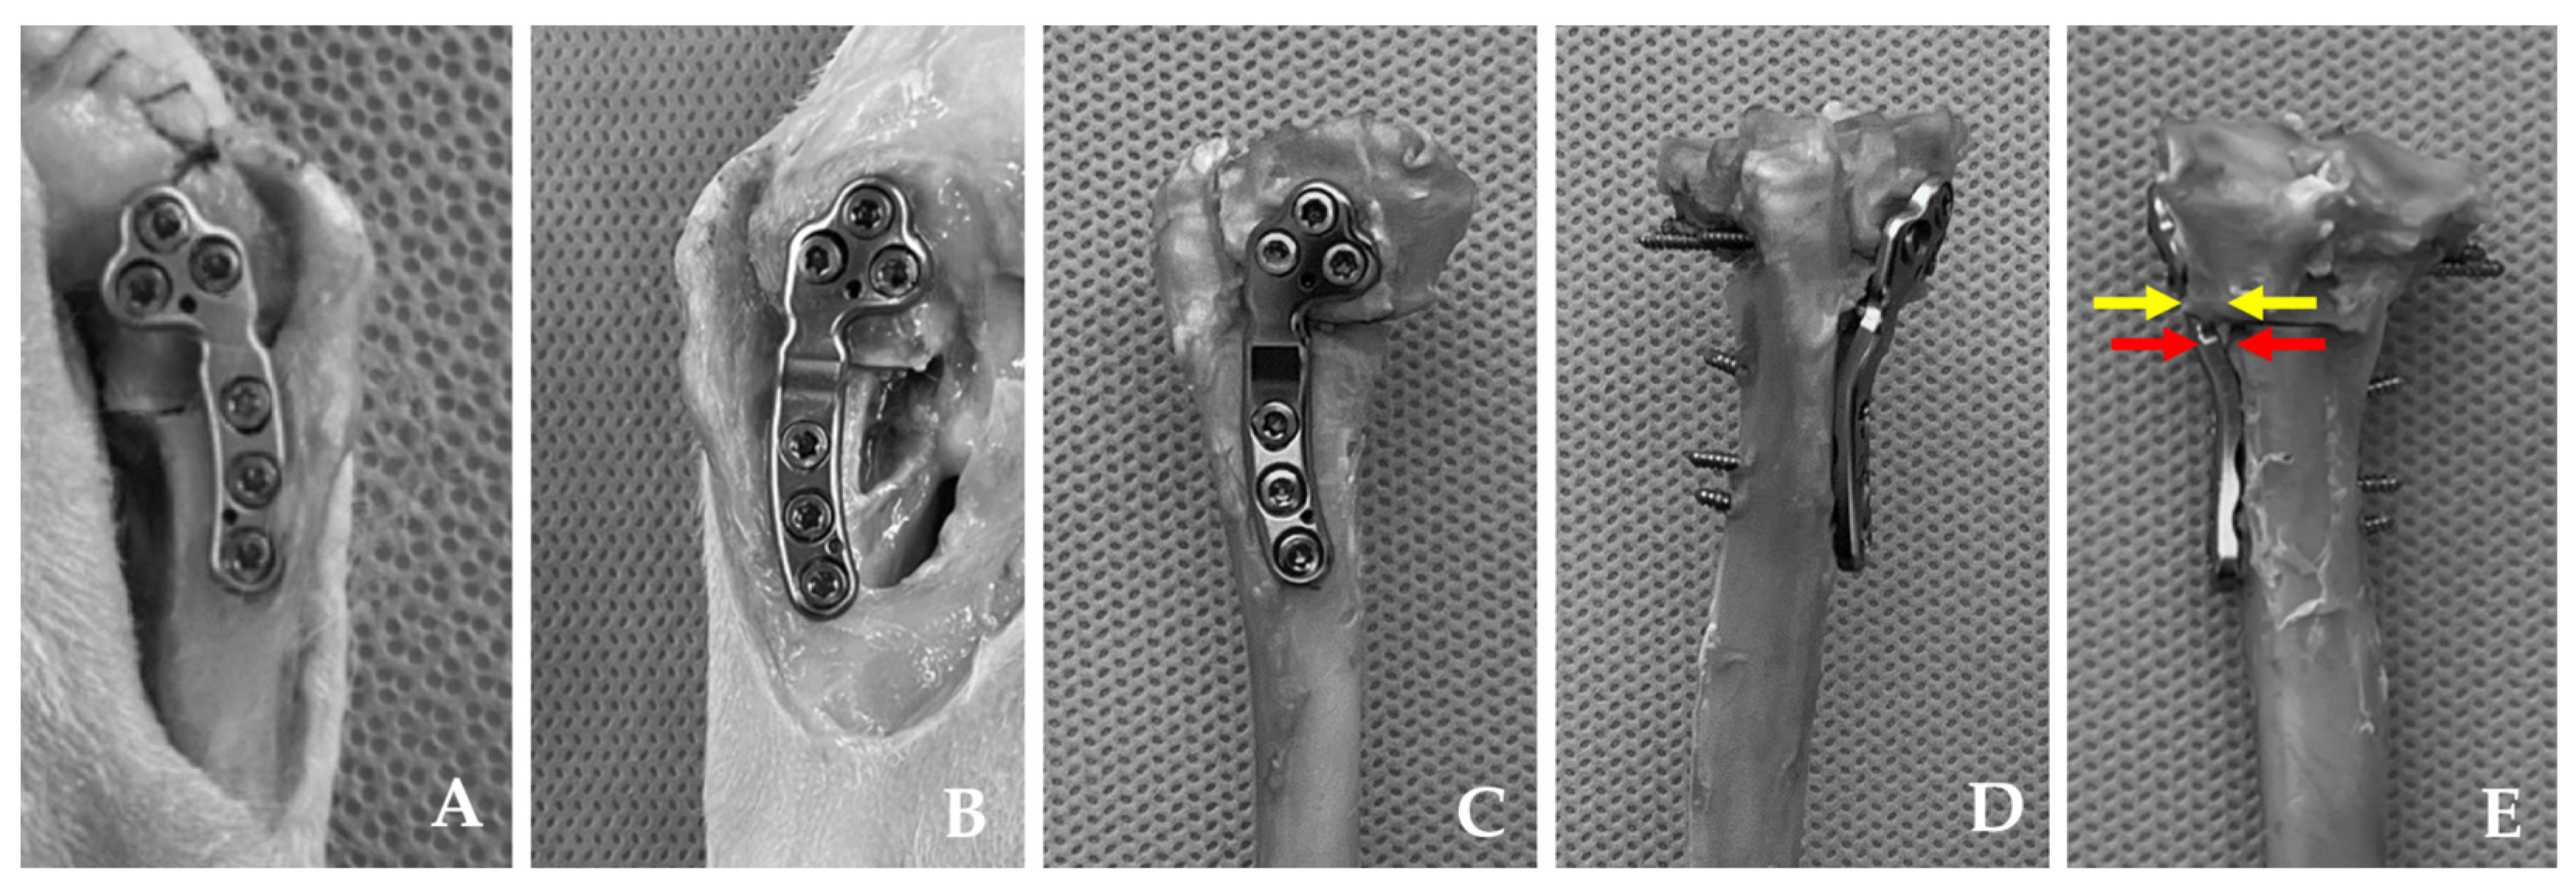

2.2. Specimens

2.3. Surgical Procedures

2.4.2. Compression Test